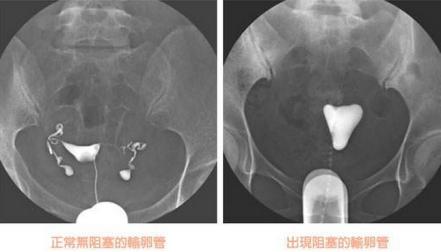

输卵管造影是用来检查女性输卵管通畅与否的一种检测方法。目前,输卵管造影是临床上应用较为广泛的方法之一。造影是通过导管经阴道、宫颈、子宫腔直接插向子宫角的输卵管开口处,对着输卵管推注造影剂而使输卵管显影,进而了解输卵管是否通畅、阻塞部位及宫腔形态的一种检查方法。